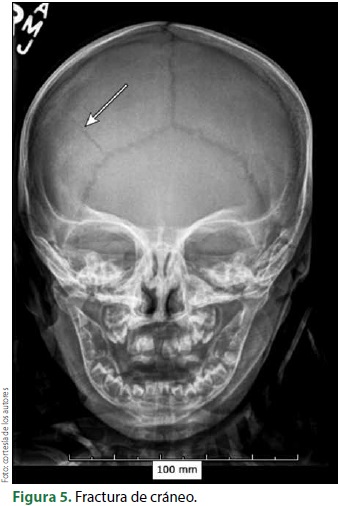

En la mayoría de los casos, además de la expresión visible en la piel y en las mucosas, puede existir una lesión ósea en cráneo, costillas, vértebras o miembros superiores e inferiores. Por supuesto, también se puede ocasionar alguna lesión en los órganos de la cavidad craneal, la cavidad torácica, la cavidad abdominal y pélvica7. En los casos de lesión ósea, la expresión habitual es la presencia de fracturas de grado y gravedad variable. De esta manera, la radiografía se convierte en la "voz del niño maltratado"8.

Una característica agregada en estos pacientes es que el trazo de la fractura habitualmente no se explica por el mecanismo que plantea el familiar o la persona encargada del menor. Así, el médico no solamente localiza la lesión, también debe entender y explicar el mecanismo probable de ésta. Por ejemplo, una fractura helicoidal en un hueso largo de una extremidad se explica por la torsión de éste y no por una caída de la altura del menor, como frecuentemente lo plantea el adulto.

La lesión de ciertos huesos como pueden ser las apófisis espinosas, costillas o las clavículas, pueden ser el resultado de un puntapié, compresión extrema de la caja torácica o por un golpe directo contra una superficie dura como la pared o el suelo (figuras 4-5).